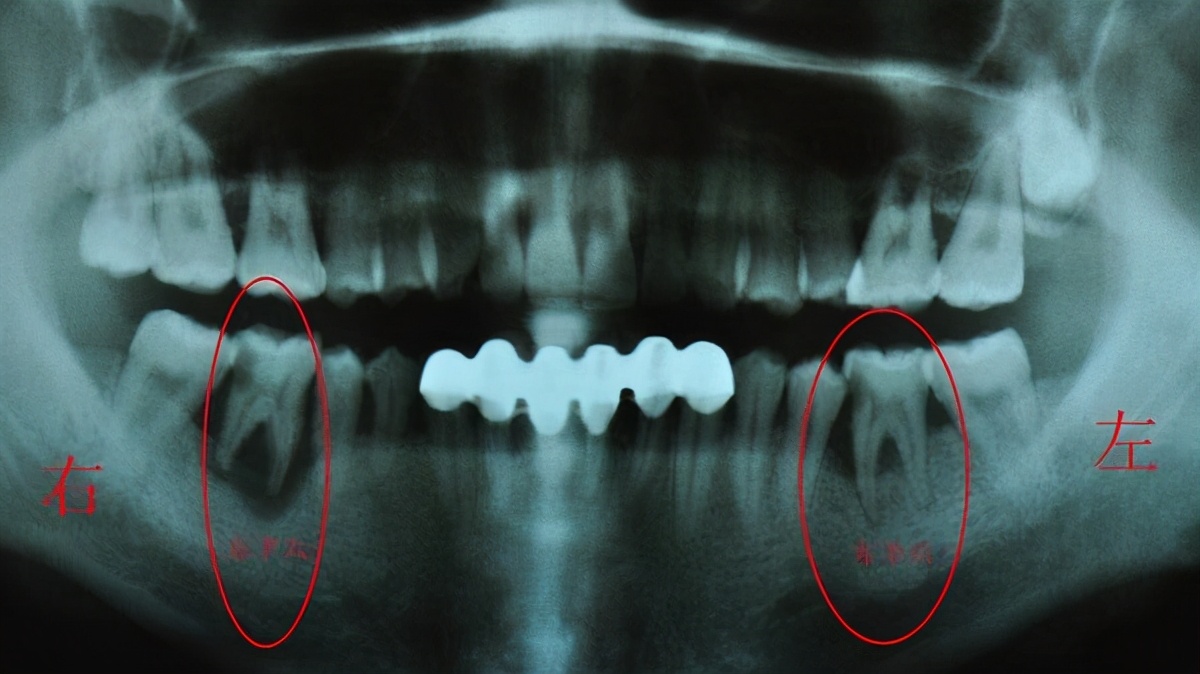

确实,在正常情况下,牙槽骨的吸收与新生都是平衡的,牙槽骨高度保持不变。但当骨吸收增加,或骨新生减少或两者并存时,就会发生骨丧死,使牙槽骨高度降低,即牙槽骨“变薄”。这在临床上被称为牙槽骨吸收,都是后天“作”的结果。

牙周病炎是造成牙槽骨变“薄”的主要原因之一。牙菌斑中的细菌会入侵到牙周组织引起炎症,造成牙龈萎缩。牙龈一萎缩,靠牙龈供给营养的牙槽骨就会出现营养不良,时间一长,牙槽骨萎缩变薄。

长期缺牙,会导致缺牙区内的牙槽骨因缺乏生理性刺激而发生骨质吸收,牙槽骨高度降低,宽度变窄。